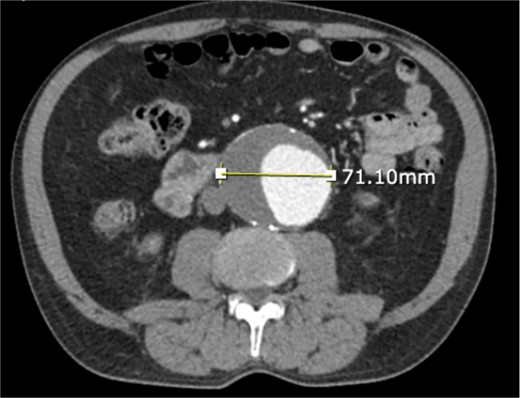

A 71-year-old male with a past medical history of hypertension, dyslipidemia, and renal insufficiency presented to the emergency department with headache and dizziness that began after performing manual labor. The only abnormality with initial vital signs was an elevated blood pressure. Physical exam revealed a palpable pulsatile mass in the epigastrium. An electrocardiogram showed normal sinus rhythm with signs of previous inferior and anterolateral infarcts. Troponin levels were within normal limits. Further workup with an echocardiogram demonstrated left ventricular hypertrophy and ejection fraction (EF) of less than 50%. Due to the pulsatile abdominal mass, a computed tomography (CT) of the abdomen without contrast, and subsequent CT angiogram of the abdomen and pelvis, was completed that demonstrated a 7.1-cm infrarenal AAA with a large mural thrombus causing luminal narrowing (Figs 1 and 2).

CT angiogram of abdominal aorta and iliofemoral artery axial view.